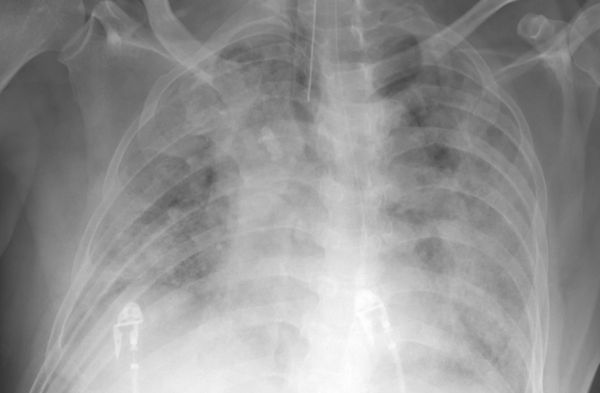

中國大陸先前將「新冠肺炎」改名為「新冠病毒感染」,但仍有許多患者出現了肺炎症狀

,甚至還傳出多起「白肺」病例。對此,大陸國家衛健委醫政司司長焦雅輝表示,從2022

年的數據來看,出現肺炎的佔比相當低,不到10%,大概是8%左右,「我們國家人口基數

大,再低的比例,變成絕對值,都是一個不小的數目。」

大陸先前將「新冠肺炎」改名為「新冠病毒感染」,但仍有許多人出現肺炎症狀,甚至傳

出多起「白肺」病例。對此,焦雅輝指出,從2022年國家的Omicron臨床病例的分型情況

來看,出現肺炎,也就是「普通型」的佔比還是相當低的,不到10%,大概是8%左右。

焦雅輝強調,現在因為感染的基數大了,出現肺炎的絕對數值一定是大的,「因為我們國

家人口基數大,再低的比例,變成絕對值,都是一個不小的數目。」

焦雅輝說,從臨床上看到的病情來講,雖然大家感覺現在肺炎比較多,但是從臨床上過來

的訊息看,同樣是肺炎,現在的肺炎和3年前的肺炎,影響程度是不一樣的,「現在的肺

炎絕大多數經過及時治療和干預,是可以拉回來的,也就是說可以治好的。」